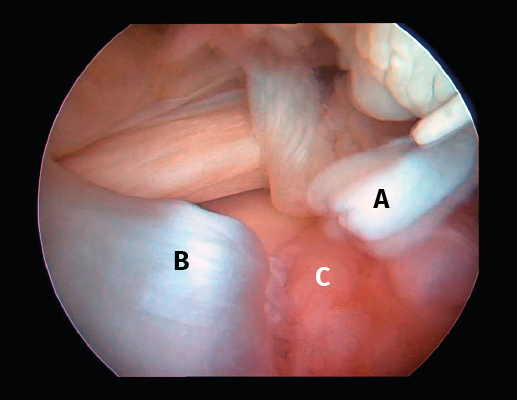

Figura 4. Rotura de supra- e infraespinoso en forma de L invertida con presencia de 2 capas. A: tendón supraespinoso; B: tendón infraespinoso; C: cabeza humeral.

Figura 5. Rotura de tipo C1. A: rotura pequeña de espesor completo del supraespinoso; B: cabeza humeral.

Sin embargo, las clasificaciones basadas en el tamaño de la rotura deben ser bidimensionales, ya que la visión unidimensional puede ser engañosa, al mostrar el tamaño de la rotura solo desde el plano anteroposterior(4). Por esta razón, proponemos el sistema de clasificación del manguito posterosuperior sugerida por Snyder, que aporta información no solo del tamaño, sino del número de tendones afectados y la presencia de tejido cicatricial(7). En las lesiones de tipo C1 la lesión atraviesa todo el espesor del tendón y en el eje transversal es pequeña y punzante (Figura 5). Las de tipo C2 son roturas de espesor completo pero la distancia entre los extremos de la rotura es menor de 2 cm con escasa retracción (Figura 6). En las de tipo C3 la rotura afecta en sentido transversal entre 3 y 4 cm con mayor retracción implicando 2 tendones (Figura 7). Y las de tipo C4 son la rotura masiva del manguito de los rotadores con una afectación de espesor completo de toda la anchura de 2 o más tendones asociando importante retracción (Figura 8).

Figura 8. Rotura de tipo C4. A: rotura masiva del tendón supraespinoso con presencia de degeneración grasa; B: glena; C: rotura masiva del tendón infraespinoso; D: cabeza humeral.